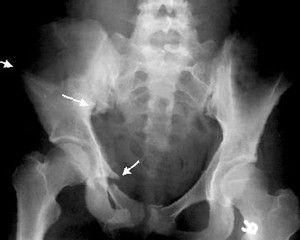

Главный метод инструментального обследования – рентгенография. В некоторых случаях для детальной визуализации применяются разные виды томографии. Именно благодаря тщательной диагностике можно определить, насколько тяжелый осколочный перелом, какова степень смещения осколков.

Многооскольчатый перелом, т.е. когда образуется много костных отломков, может произойти в любой части тела, в связи с чем, целесообразно выделить две большие группы таких травм:

- осколочные травмы таза и нижних конечностей.